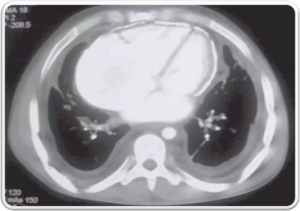

• Rasmussen aneurysm is a pseudoaneurysm that results from weakening of the pulmonary artery wall by adjacent cavitatory TB.

CECT obtained shows cavitatory consolidation with air-crescent sign in left upper lobe.